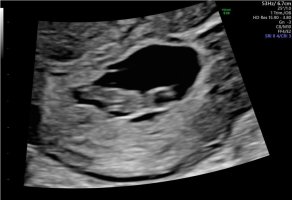

Gravid 7+5 og første ultralyd

det er bare én inni her, den ble målt til 7+3, men tror jeg står ved min utregning til otul. Det blir så mange apper å endre på hver gang

Hun tok utvendig ul, faktisk.

Skjønneste lille